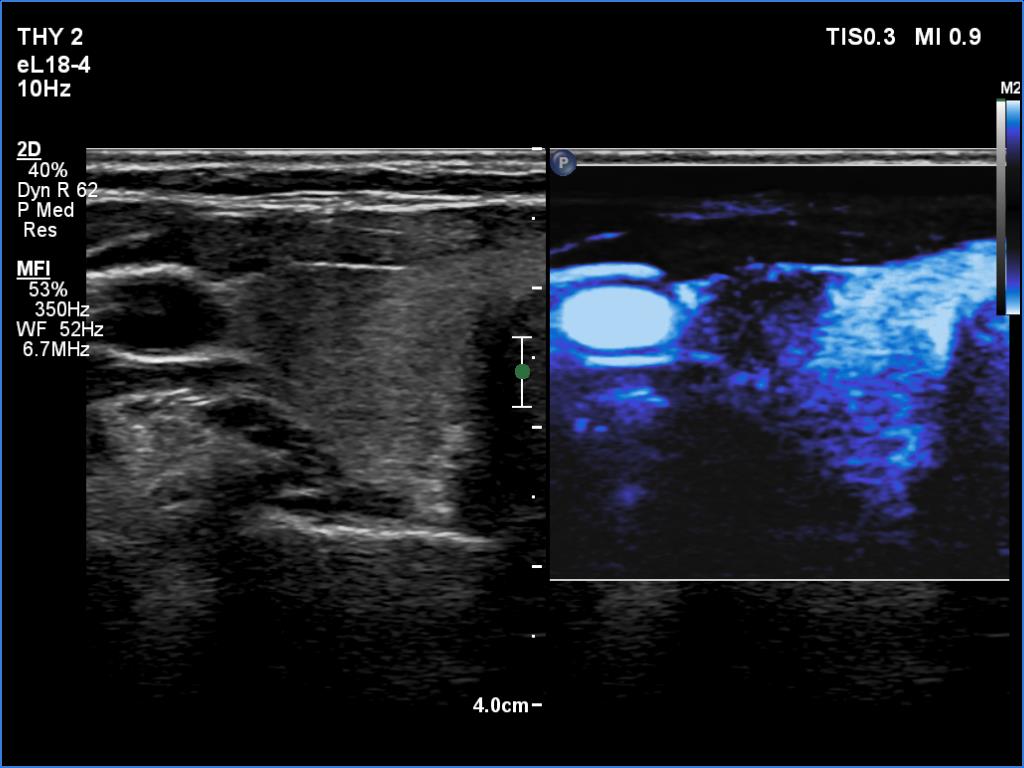

Follow-up examination five years later (ultrasonographic picture 4)

Right lobe, transverse scan, microflow imaging.